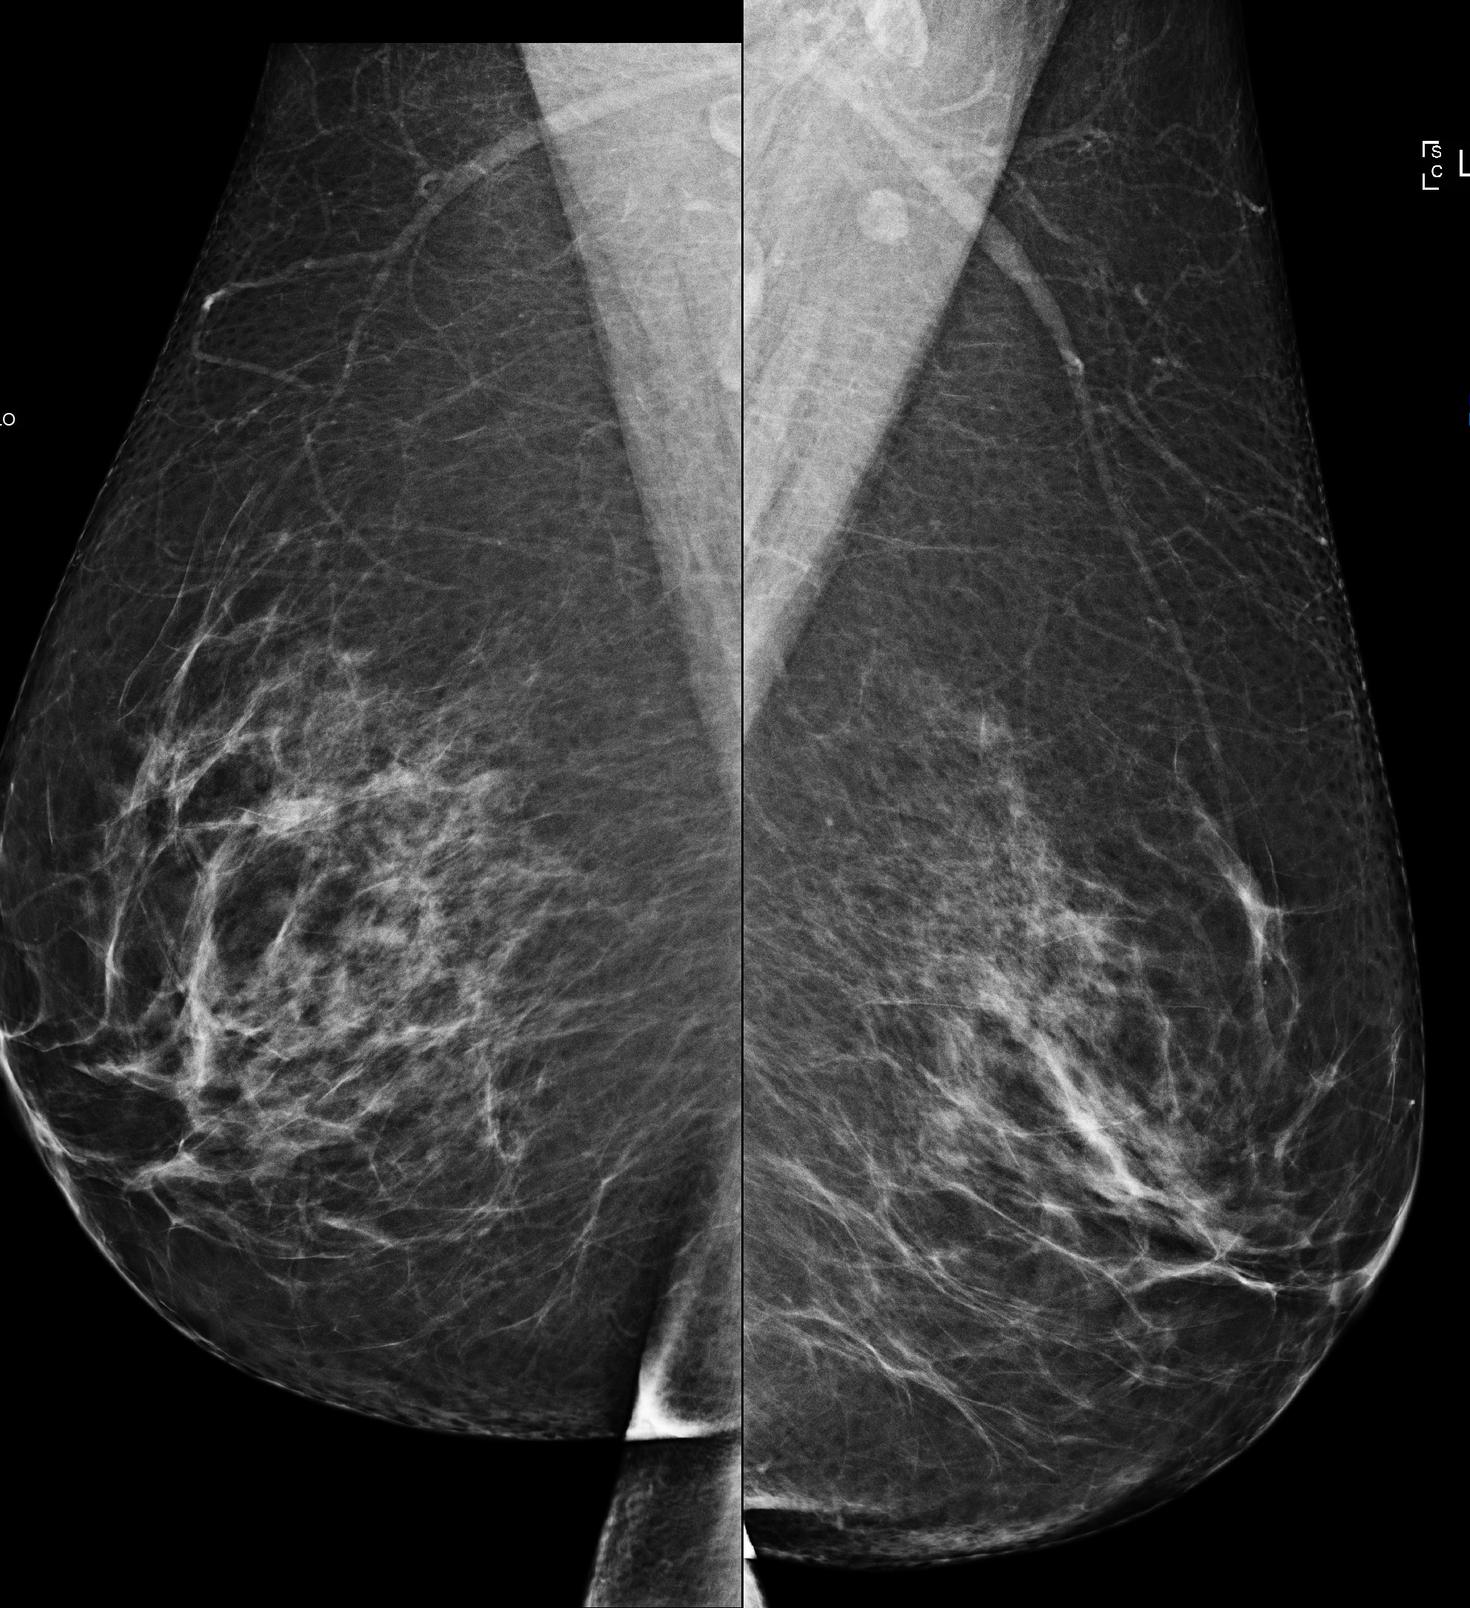

Mammogram

Vecteezy